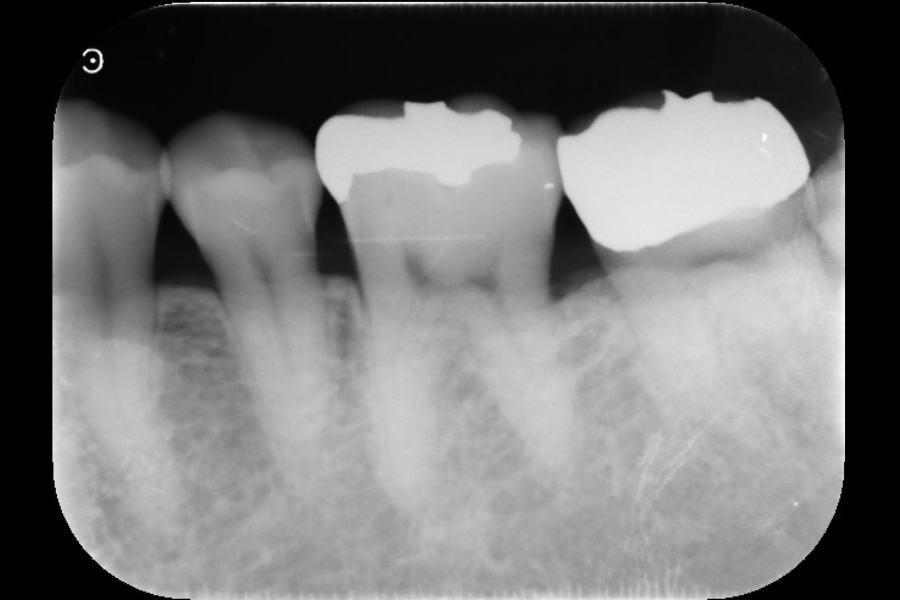

左上奥歯の歯ぐきが腫れて、噛むと痛い

【歯周組織再生療法】

- 主訴

- 左上奥歯の歯ぐきが腫れて、噛むと痛い

- 治療内容

- 左上4遠心と左上6近心に垂直性骨吸収が認められたためエムドゲインと骨補填材を用いて歯周組織再生療法を行った

- 治療に伴うリスク

- 歯肉退縮、知覚過敏